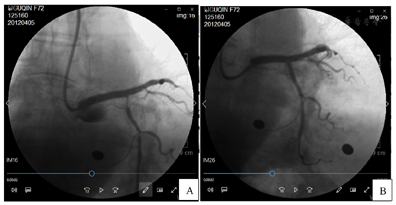

立即于前降支近段狭窄处植入火鸟3.5 mm×23.0 mm药物洗脱支架1枚,其后自前降支近段贯穿左主干开口植入火鸟4.0 mm×23.0 mm药物洗脱支架1枚,两支架重叠约3 mm。造影复查,左主干血管夹层消失,前降支近段未见明显狭窄,前降支及回旋支远段血管前向血流TIMI 3级,但回旋支开口处出现局限性狭窄,最重处约90%。

考虑回旋支开口处出现壁内血肿可能性大。其后使用第2条Runthough NS导引导丝进入回旋支远段血管,2.0 mm×15.0 mm顺应性球囊(sprinter)10个大气压先后扩张回旋支中段狭窄处和回旋支开口支架网眼处。其后自回旋支中段至开口狭窄处由远及近先后精确定位植入2枚火鸟2.5 mm×18.0 mm药物洗脱支架,两支架重叠约3 mm。其后于左主干及前降支近段支架内使用4.0 mm×12.0 mm非顺应性球囊(sprinter)18个大气压扩张。造影复查,左主干、前降支及回旋支支架内未见明显残余狭窄,前向血流TIMI 3级(图3)。手术期间患者每3~5分钟出现1次三度房室传导阻滞并心室停搏,每次均进行心脏按压、静推阿托品后恢复窦性心律,至冠脉介入治疗结束时共发生6次。其后植入临时起搏器,起搏频率60次/min(图4)。